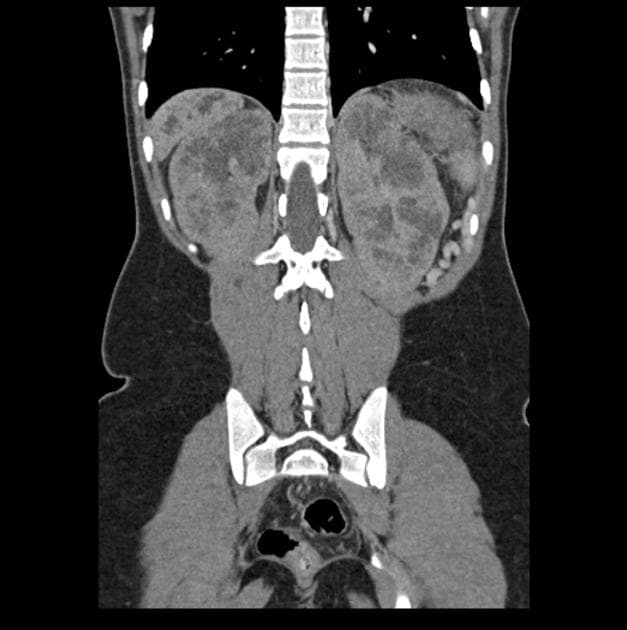

Ca bệnhBệnh Caroli kèm thận bọt tủy và vôi hóa thận

- MRI cho thấy các giãn nang dạng nang ở đường mật trong gan và ngoài gan kèm theo nhiều sỏi lớn.

- Phát hiện tình cờ thận bọt tủy (medullary sponge kidney).

- MRI cho thấy các giãn nang dạng nang ở đường mật trong gan và ngoài gan kèm theo nhiều sỏi lớn. Phát hiện tình cờ thận bọt tủy (medullary sponge kidney). Siêu âm thận (Renal USG) thực hiện sau đó cũng cho thấy vôi hóa thận (nephrocalcinosis).

Bệnh Caroli kèm thận bọt tủy (medullary sponge kidney) và vôi hóa thận (nephrocalcinosis)

Bệnh Caroli là một bệnh lý bẩm sinh hiếm gặp, đặc trưng bởi sự giãn ra từng đoạn không do tắc nghẽn của các ống mật trong gan, đôi khi có thể lan ra các ống mật ngoài gan. Bệnh làm tăng nguy cơ ứ đọng dịch mật, hình thành sỏi, viêm đường mật tái phát và nguy cơ ung thư đường mật cao hơn đáng kể. Trên MRI, hình ảnh đặc trưng thường thấy là 'dấu chấm trung tâm' do các nhánh tĩnh mạch cửa nằm trong lòng các ống mật giãn. Việc đồng thời xuất hiện thận bọt tủy và vôi hóa thận trong trường hợp này là bất thường, nhưng làm nổi bật khả năng liên quan đến các hội chứng phát triển như bệnh thận đa nang kiểu lặn trên nhiễm sắc thể thường (ARPKD) hoặc hội chứng oro-facial-digital type 1. Thận bọt tủy là tình trạng lành tính, liên quan đến sự giãn dạng nang của các ống góp ở tủy thận, thường dẫn đến vôi hóa thận do ứ đọng nước tiểu và tăng calci niệu. Sự kết hợp giữa các thay đổi nang ở đường mật và thận cần gợi ý đến các rối loạn toàn thân hoặc di truyền, và bệnh nhân có thể được hưởng lợi từ tư vấn di truyền và tầm soát các bệnh lý liên quan.